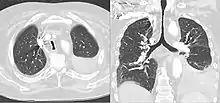

CT scan of a saber-sheath trachea in a patient with COPD

A saber-sheath trachea also known as scabbard trachea is a trachea that has an abnormal shape. The posterior area of the trachea increases in diameter while the lateral measurement decreases.